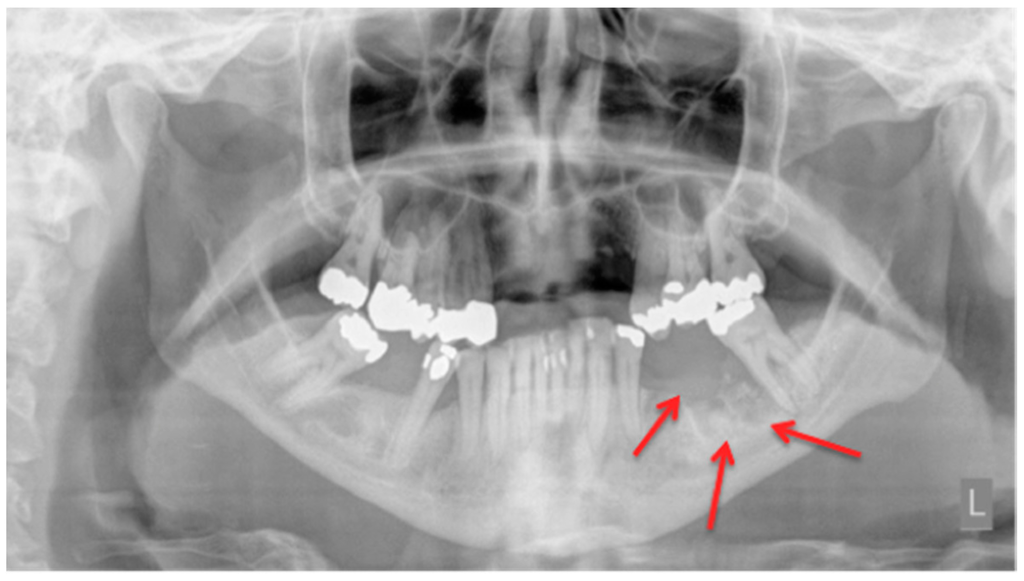

In a daily routine, a clinical examination and a radiograph are the minimum examinations required in order to detect lesions and to provide data for a follow-up appointment. For Marx et al., panoramic imaging is the image of choice for a routine dental assessment in these patients [13]. Figure 1, Figure 2 and Figure 3 exemplarily depict typical findings of panoramic radiographs.

Figure 1.

Panoramic radiograph: Patient: 48 years old, female, metastatic breast cancer, zoledronic acid. Red arrows point to the necrotic area. The corresponding magnetic resonance imaging (MRI) images are shown in Figure 6 and Figure 7. American Association of Oral and Maxillofacial Surgeons (AAMOS) staging: stage 2.

Rocha et al. were able to show that patients who “are treated with zoledronate presented a statistically significant increase in the number of radiographic abnormalities compared with the control group” [14]. Although their sample size was not very large and only 30 patients were treated with zoledronic acid early bone alteration was found in these patients. As stated by Arce et al., conventional anatomic imaging is easily accessible but bone changes and radiographic findings can have a lag time of up to two weeks [15]. Phal et al. found in their study that all patients showed osseous sclerosis. The alveolar margin was involved in two-thirds of the patients. Lamina dura thickening, full-thickness sclerosis, poor/non-healing extraction sockets, widening of the periodontal ligament space, osteolysis, as well as sequestra, fistula, soft tissue thickening, and periosteal new bone formation were also found and described [12]. Patients who received follow-up imaging showed progressive sclerotic changes leading to possible narrowing of the mandible canal [12]. A study published by Torres et al. was able to show that in panoramic radiographs the “mean mandibular inferior cortical bone thickness (MICBT) of patients with BRONJ was significantly higher compared to patients without BRONJ taking BPs, and mean MICBT of patients without BRONJ taking BPs was higher than that of controls”. They could also show that “among patients taking zolendronate, there was a correlation between MICBT and cumulative dose” [16]. An animal model (rats) also showed changes in the bone after animals were treated with a zoledronic acid and dexamethasone followed by extraction of mandibular or maxillary molars. The radiographs from these animals showed “poor definition of the alveolar ridge with mixed radiodensity” [17]. A prospective study from Stockmann et al. revealed detectability of MRONJ lesions was 54% for panoramic radiographs, 96% for CT, and 92% for MRI scans [18]. Their study acquired all images 10 days prior to surgery. The images were assessed by two experienced radiologists who were unaware of the clinical findings. Panoramic radiographs were only evaluated in regard to possible identification of all jaw regions affected by MRONJ [18]. Treister et al. stated that they found a “trend towards higher stage with greater radiographic findings”, but it was not significant [19].

To sum up, we agree with Stockmann et al.’s conclusion: “even if BONJ lesions can be detected on panoramic radiographs, an adequate assessment of the extent of BONJ is not possible” [18], and therefore panoramic imaging is usable, but in severe cases must be followed by further diagnostics.